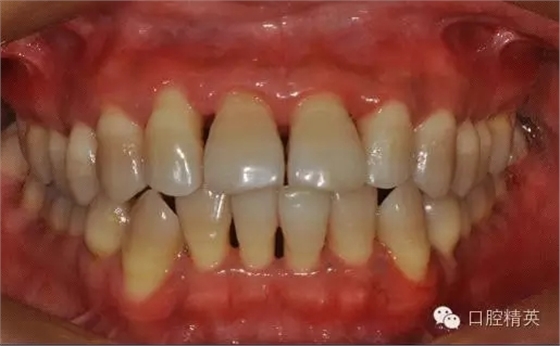

治療后:炎癥得到控制,牙周袋已消除,松動(dòng)度有所改善。